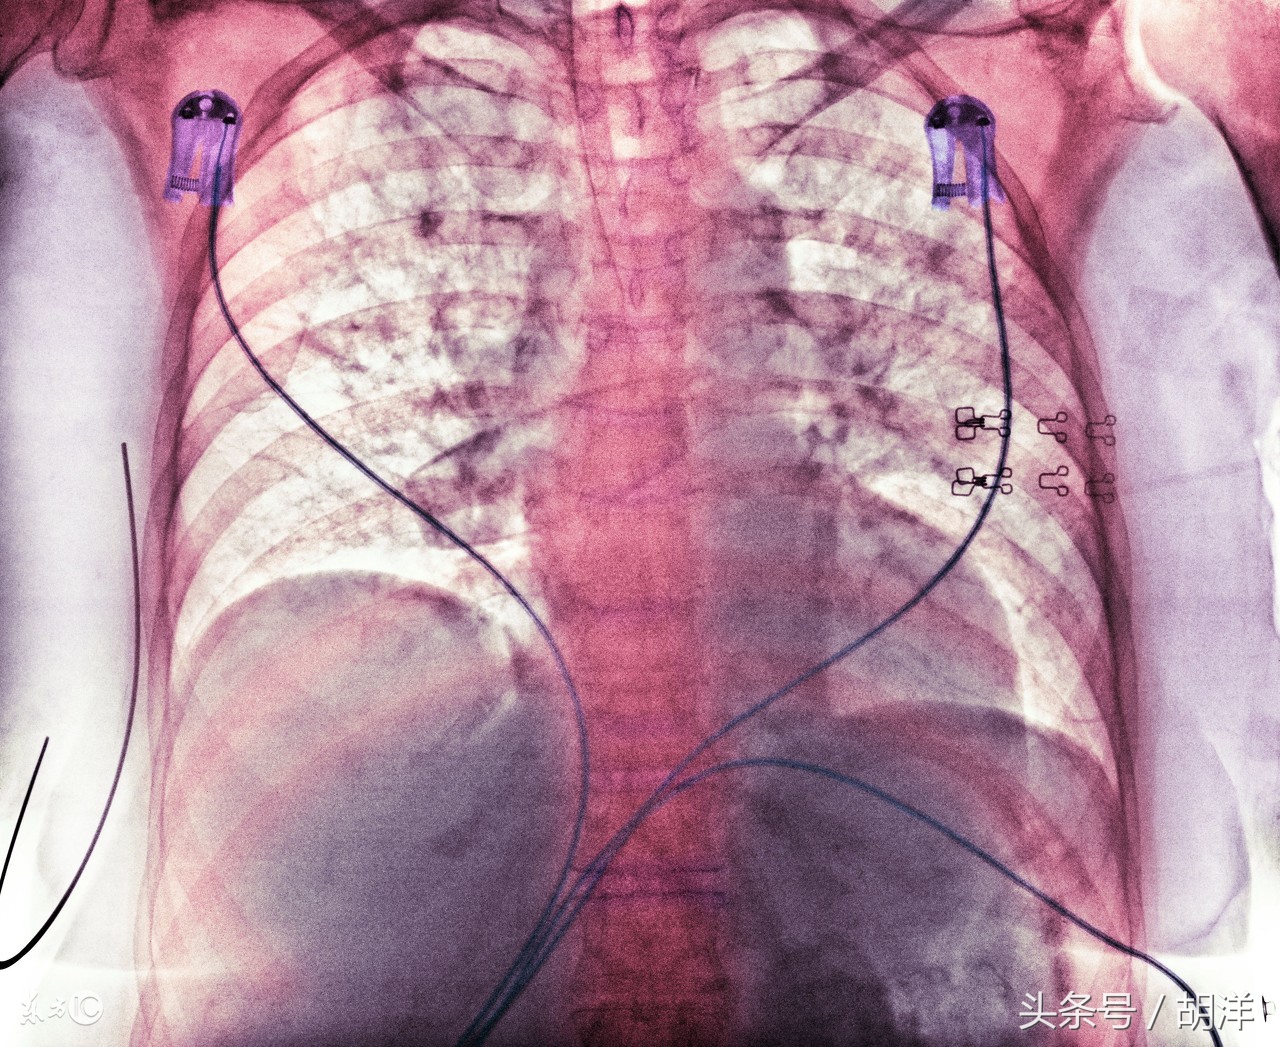

对于内科有创检查不能明确,同时又不想做手术的患者,可以进行诊断性的抗结核治疗,这种情况一般都要在普通的抗感染治疗无效之后,临床血液检查以及胸部影学检查,都支持结核的情况下使用,治疗过程中,复查胸部ct,观察病灶变化,如果有缩小了,就证明是结核,如果没有缩小还是要进行手术活检检明确诊断。